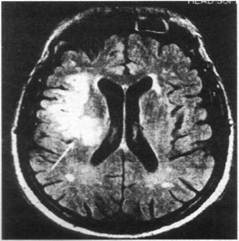

МРТ головного мозга больного с острым территориальным инфарктом правой лобно-височной области через 22 ч от начала заболевания (Т2ТИРМ-взвешенное изображение, аксиальная плоскость, срез на уровне тел боковых желудочков):

в правых лобной и височной долях визуализируется неправильной формы гиперинтенсивный очаг инфаркта однородной структуры с четкими контурами (показано стрелкой)